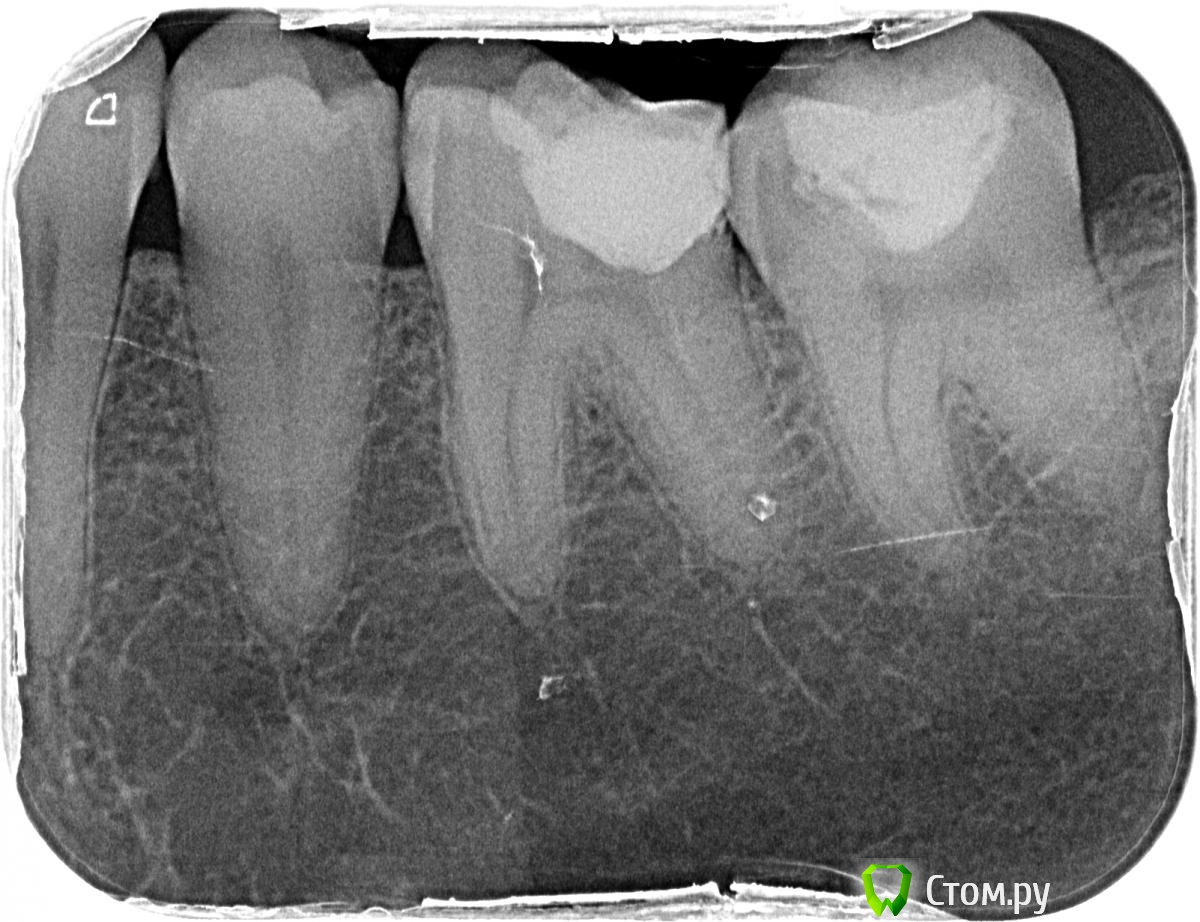

Scrabble Опубликовано 9 апреля, 2014 Поделиться Опубликовано 9 апреля, 2014 (изменено) Десна ТАК болеть не может. Сделайте тогда хотя бы актуальную ОПТГ-мы посмотрим, как 36, 37, 27 выглядят сейчас. И сустав заодно. Изменено 9 апреля, 2014 пользователем Scrabble 1 Ссылка на комментарий

pacient7 Опубликовано 11 апреля, 2014 Автор Поделиться Опубликовано 11 апреля, 2014 Я прикрепил последний снимок, на котором видны нижняя левая шестерка и семерка.А панорамный точно нужен, или лучше сделать детальный снимок верхней семерки? Ссылка на комментарий

Korel Опубликовано 11 апреля, 2014 Поделиться Опубликовано 11 апреля, 2014 (изменено) А панорамный точно нужен? Понимаете, я сам не знаю ТОЧНО, что Вам нужно. Пока могу только предполагать (предположение изложил Выше , как и совет).На представленном последнем снимки есть кое какие проблемы, НО, опять же: думаю они не связаны с причиной.Поэтому ОПТГ не повредит точно, даже если и не поможет найти истинную причину Ваших болей, то понадобится позже , когда будет поставлен диагноз, начнётся осн. лечение и по ней (ОПТГ) Вы со спокойной душой будете решать проблемки, связанные с зубами. Изменено 11 апреля, 2014 пользователем Korel Ссылка на комментарий

pacient7 Опубликовано 11 апреля, 2014 Автор Поделиться Опубликовано 11 апреля, 2014 На представленном последнем снимки есть кое какие проблемыА какие конкретно есть проблемы с нижней шестеркой и семеркой на снимке? Семерка до сих пор реагирует на холодный сок (10 дней прошло после лечения). Шестерка до сих пор болит при нажатии (боьше чем три месяца прошло после лечения). Надо ли их перелечивать? Ссылка на комментарий